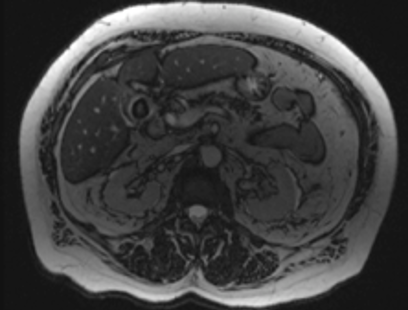

Given the patient’s elevated LFT results, including an elevated bilirubin suggesting obstruction and concerning for choledocholithiasis, magnetic resonance cholangiopancreatography (MRCP) was performed and confirmed the ultrasonography results (Figure 3). One large gallstone and other smaller stones were present in the gallbladder. There was some minimal fluid in or inflammation in the gallbladder fossa, nonspecific but suggesting cholecystitis. Endoscopic retrograde cholangiopancreatography (ERCP) confirmed the presence of a gallstone and inflammatory findings consistent with acute calculous cholecystitis (Figure 4). No imaging modality gave a clear indication of the presence of a cholecystoenteric fistula (CEF).

Figure 3. MRCP showing a large gallstone with gallbladder wall inflammation and thickening consistent with the diagnosis of acute cholecystitis. CDF was not identified.